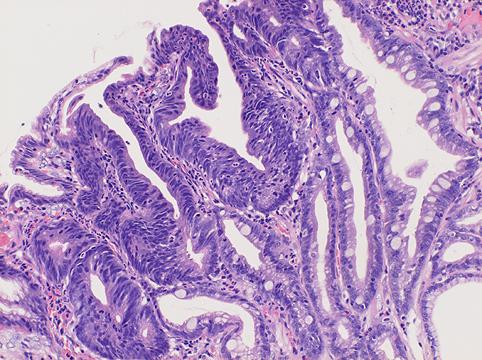

疾患(病理主体)の分類悪性上皮性腫瘍/腺癌

部位(臓器別)胃(部位)/前庭

検査方法ミクロ

腫瘍の肉眼分類0型(表在型)/IIc型(IIc)

病変の最大径(ミリ)1〜9

腫瘍の深達度m